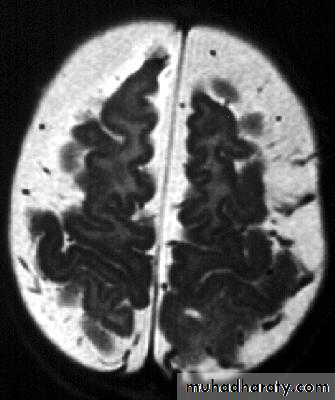

• B. Radiological Investigations:• CT or MRI is the investigation of choice.

• CT Brain is performed with and without contrast.

• MRI is done with gadolinium enhancement.

• They will show a single (or multiple) space occupying lesion that is well delineated with an enhancing wall, with variable surrounding oedema.

Brain Abscess CT without contrast

Brain Abscess CT with contrast

Brain Abscess MRI